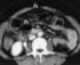

Trauma with duodenal perforation

Gastrointestinal perforation, also known as ruptured bowel, is a hole in the wall of part of the gastrointestinal tract. The gastrointestinal tract includes the esophagus, stomach, small intestine, and large intestine. [Source: Wikipedia ]